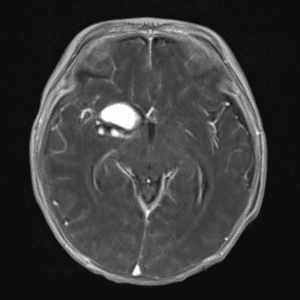

Case #42

Giant cerebral aneurysm